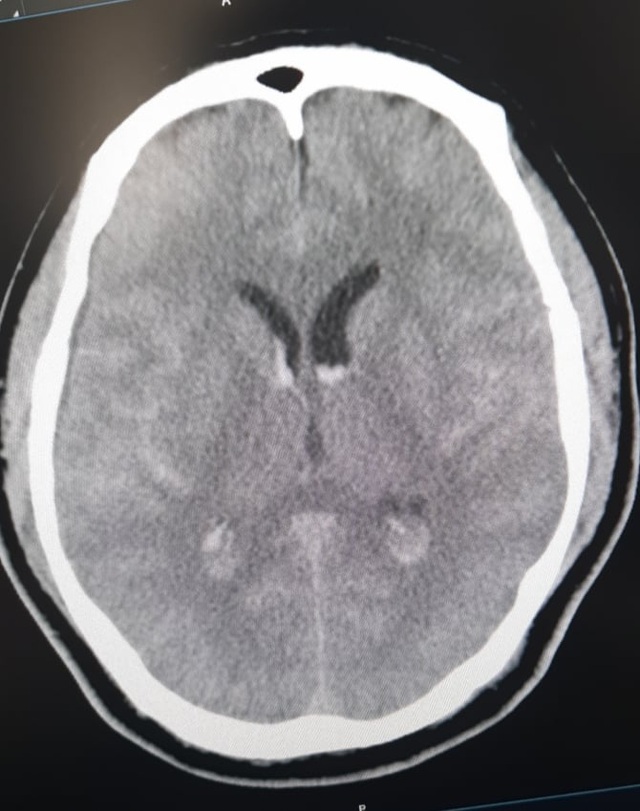

Ngày 9/12/2020, bệnh nhân cùng nhóm đối tác đang chơi gôn ở Hòa Bình thì đột ngột đau đầu dữ dội, buồn nôn và nôn nhiều. Bệnh nhân được đưa vào cấp cứu tại Bệnh viện tỉnh Hòa Bình, được chụp CT sọ não và chẩn đoán chảy máu dưới nhện và được chuyển lên Trung tâm Đột quỵ, Bệnh viện Bạch Mai.

Ngay khi tiếp nhận, các bác sĩ Trung tâm Đột quỵ đã nghi ngờ nguyên nhân chảy máu dưới nhện là do dị dạng mạch não. Bệnh nhân được đi chụp CTA - chụp mạch não phát hiện chảy máu dưới nhện lan tỏa - chảy máu não thất do vỡ phình lóc tách động mạch đốt sống phải đoạn V4. Đây là một tổn thương có vị trí khó, phức tạp.